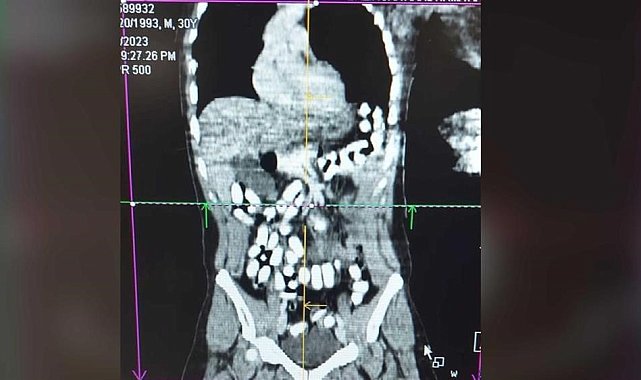

Erzincan'da midesinde 977,60 gram Afyon sakızı taşıyan şahıs tutuklandı.Erzincan İl Emniyet Müdürlüğü Narkotik Suçlarla Mücadele Şube Müdürlüğü ekiplerince, uyuşturucu ve uyarıcı maddelerin imal ve ticareti veya temini, gerek kullanmak için satın alınması, kabul edilmesi veya bulundurulması, gerekse de kullanımının kolaylaştırılması veya özendirilmesi eylemlerine ilişkin yapılan çalışmalarda; Türk Ceza Kanunu 188'inci maddesi "Uyuşturucu veya uyarıcı madde imal ve ticareti" suçuna ilişkin polis uygulama noktasında durdurulan, bir araçta bulunan A. H. isimli İran uyruklu şüpheli alınan iç beden muayenesi kararına istinaden hekim gözetiminde çekilen tomografi neticesinde mide ve bağırsak kısmında 126 adet kapsül halinde daralı ağırlığı ise 977,60 gr Afyon sakızı ve 25 adet Metadon hap ele geçirildi.Midesinde uyuşturucuyla yakalanan A.H. ise gözaltı işlemlerinin ardından çıkarıldığı mahkemece tutuklanarak cezaevine gönderildi.